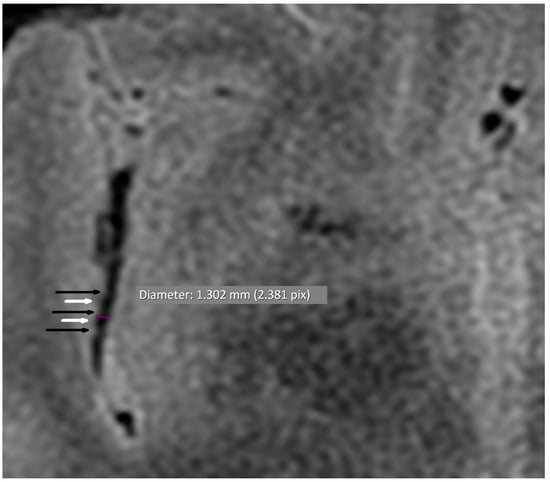

3.1. Vascular Alterations

| Alternating narrowing and dilatation in secondary vascular branches | 13/38 (34.2) | 1/38 (2.6) | <0.001 |

| Alternating narrowing and dilatation in tertiary vascular branches | 13/38 (34.2) | 1/38 (2.6) | <0.001 |

| Alternating narrowing and dilatation in secondary and tertiary vascular branches | 16/38 (42.1) | 2/38 (5.3) | <0.001 |